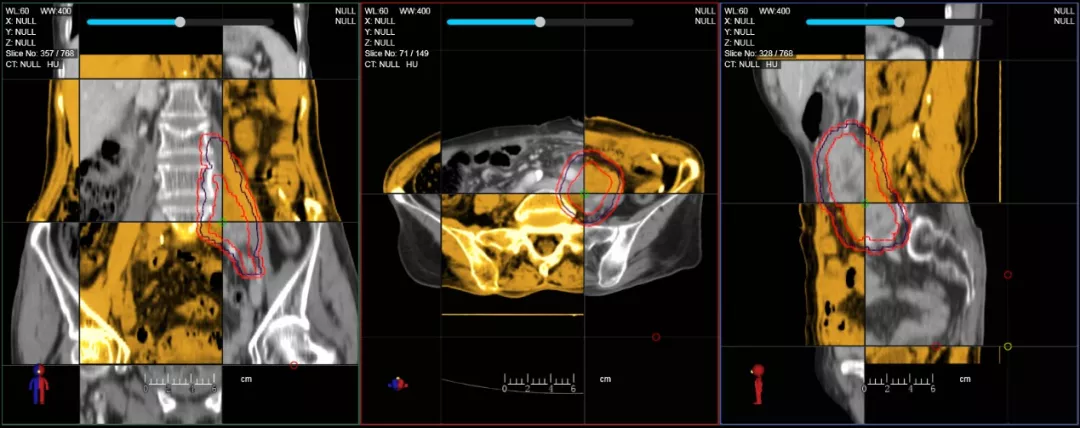

一體化CT-linac讓自適應放療ART概念變?yōu)楝F實?;颊呷煶虪顟B(tài)監(jiān)控,適時在線調整治療計劃,精準控制治療劑量,為患者動態(tài)定制個體化治療方案。uAI賦能智能勾畫和自動計劃,秒級勾勒靶區(qū)和危及器官,大幅縮短自適應放療時間。

在線自適應放療流程示意圖